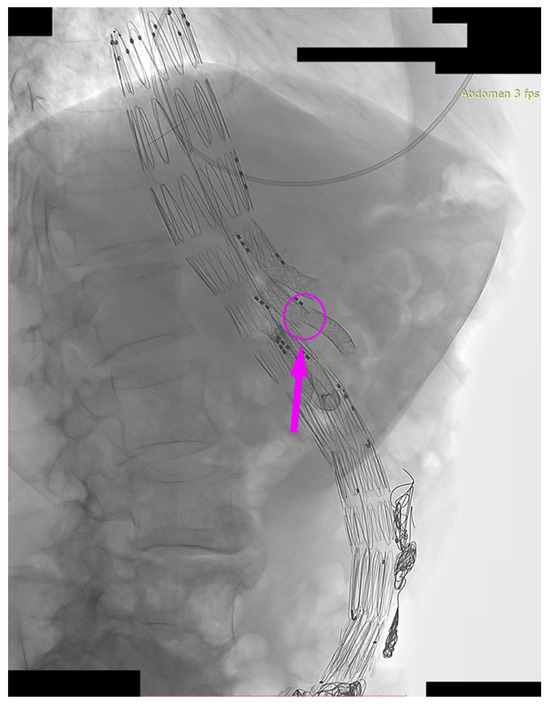

We present the case of an 82-year-old male patient who appeared in the emergency department due to progressive weakness and abdominal pain (2024). Due to a drop in blood pressure to 80/40 mmHg, a continuous infusion of norepinephrine was initiated. The hemoglobin level was approximately 5.1 g/dL. His medical history included generalized atherosclerosis, renal failure, and a thoracoabdominal aortic aneurysm (TAAA) treated with endovascular aneurysm repair (EVAR) using stent-graft implantation 4 years earlier (2020). At that time, the angio-CT scan revealed an aneurysm starting just below the celiac trunk, extending to the superior mesenteric artery (SMA) and both renal arteries (RAs). The maximum diameter of the aortic aneurysm was 51 mm; however, the left common iliac artery measured 41 mm in diameter, an indication for thoracoabdominal stent graft implantation. The aortic aneurysm itself was completely free of mural thrombus. The patient had also experienced a heart attack 16 years earlier and a transient ischemic attack (TIA) 2 years earlier. Following the stent graft implantation, he underwent multiple successful interventions to address endoleaks. One year after implantation, endovascular treatment with embolization coils was performed to eliminate leakage from the lumbar artery (LA) (2021). Three years post-implantation, he was admitted to address leakage from the inferior mesenteric artery (IMA) using embolization coils as well (Figure 1) (2023). In 2024, an X-ray and CT scan revealed a rupture in a branch of the stent graft located in the SMA in its middle part, along with an enlarged aneurysm sac (74 mm) due to the fracture and leakage (Figure 2, Figure 3, Figure 4 and Figure 5). The angio-CT scan did not reveal any contrast extravasation beyond the vessel wall. However, significant contrast leakage was visible in the area of the visceral arteries within the aneurysm sac. The implanted device was the Zenith t-Branch Thoracoabdominal Endovascular Graft, and the ruptured branch was identified as the Bentley BeGraft (Bentley InnoMed GmbH, Hechingen, Germany). Urgent surgical intervention was performed. Intraoperative angiography (IA) showed a breach in the continuity of the BeGraft material within the SMA, with contrast leakage into the aneurysm sac (Figure 6 and Figure 7). To address the leakage and restore the continuity of the SMA branch, an additional BeGraft Plus 8 × 57 mm was implanted into the damaged branch. Subsequent IA and control CT scans confirmed the elimination of leakage, restoration of stent graft continuity, and revascularization of the SMA (Figure 8, Figure 9 and Figure 10). The surgery was completed without complications, and the patient was discharged home in good general condition. The patient returned for follow-up 3 weeks after the last intervention. An angio-CT examination was performed, revealing no enlargement of the aneurysm sac (74 mm), confirming the elimination of the endoleak, and demonstrating successful revascularization of the SMA. Ongoing follow-up will be continued.

Figure 1. Thoracoabdominal branched stent-graft in the lumen of aorta and visceral arteries. Embolization coils are marked with arrows. Abdominal X-ray.